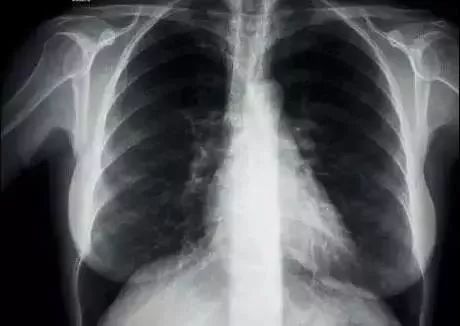

锁骨,位于胸廓前上方,横于颈部和胸部交界处, 是上肢中与中轴骨骼相连结的骨。

锁骨的 形状其实有一点像一个被拉开的“S”,而且外侧略高于内测。它构造分为胸骨端、肩峰端、和锁骨体。

胸骨端和胸骨相连,就是大家颈部下面鼓出来的那两块骨头,肩峰端就和肩胛骨相连。

锁骨体影响锁骨呈现的形状和粗细。别被图中各种各样的骨科术语搞晕了,一个人的锁骨形状是否好看一般都取决于这胸骨端和肩峰端这一头一尾的位置,以及锁骨体本身是否平滑...